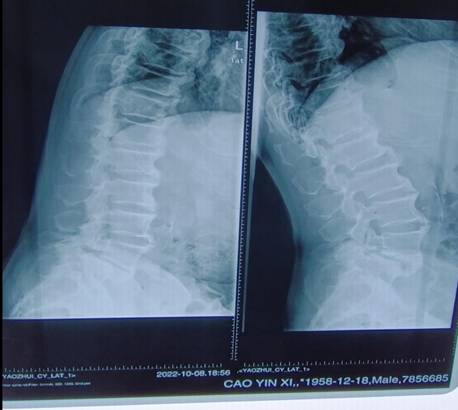

ORTHBOT脊柱机器人术前设计及术中穿刺